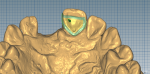

The lingual aspect of tooth No. 9 was reduced slightly and a lingual dimple was formed. An impression was taken with polyvinyl siloxane (Reprosil®, Dentsply Sirona, dentsplysirona.com), and the laboratory fabricated a stone model from the impression. The preparations on the model and wax-up were scanned to create an STL file for milling (Figure 3 through Figure 5). The laboratory milled the bridge from a commercial zirconia puck (DLMS-Crystal® Zirconia, Digital Dental, digitaldental.com). Adequate cement space was created.

The bridge was presintered at 1350°C (ie, 100°C below the zirconia sintering temperature) for 1 hour in air (Figure 6), and then the intaglio surface of the bridge was coated with an in-house aqueous-based slurry of powdered glass composition using a conventional enameling method. The glass composition was similar to conventional dental feldspathic ceramics, but its coefficient of thermal expansion was adjusted substantially so that it was similar to that of zirconia, and its melting temperature was significantly higher than that of feldspathic ceramics, while it exhibited an excellent resistance to crystallization during cooling from the sintering temperature.22,23 The powdered glass slurry was allowed to dry, and the glass-coated zirconia was subjected to infiltration and sintering at 1450°C for 2 hours in air (Figure 7).24